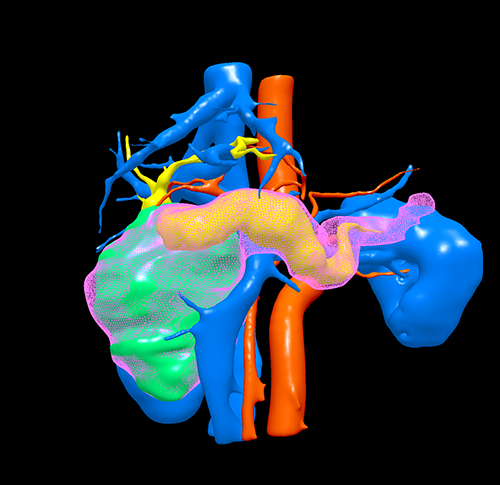

胰头囊腺瘤---胰十二指肠切除